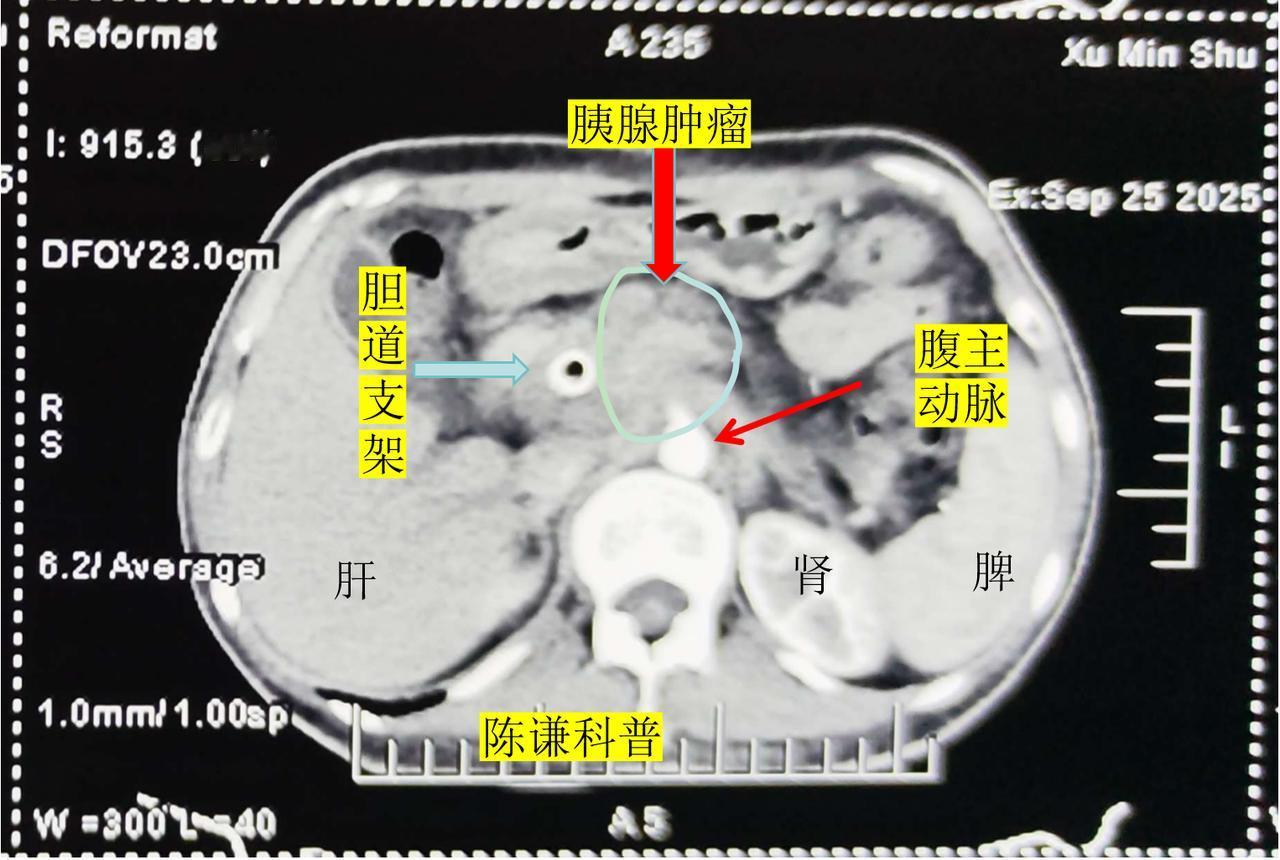

胰腺癌晚期患者如何缓解疼痛? 胰头癌是胰腺癌中最常见的类型,由于肿瘤很容易侵犯胆总管导致黄疸,并且肿瘤后方就是血管,所以很多中晚期胰腺癌都放置了胆道支架引流减黄,同时肿瘤侵犯血管和腹膜后淋巴结而失去了手术机会,对于这样的胰腺癌,大多数医院的治疗方案主要是化疗和临床试验,但是效果不理想。海扶刀治疗是一种微无创的治疗方法,可以对有胆道支架,侵犯血管,腹膜后淋巴结转移的肿瘤进行消融。 今天分享的是一名来自黑龙江的晚期胰腺癌患者,病人51岁,因黄疸在当地医院检查确诊胰腺癌,做了胆道支架,经过化疗后肿瘤有进展,伴有后腰部疼痛,然后至我们中心海扶治疗。 治疗前增强CT可以很清晰的显示,肿瘤已经包饶了腹腔干动脉,腹膜后淋巴结肿大,病灶前方是胃,右侧是十二指肠和胆道支架,后方是血管,右侧是肠道,但是经过我们海扶治疗后,肿瘤完全灭活,对血管,胆道支架没有任何影响,周边组织都保护很好,术后患者疼痛也得到明显改善。 所以,对于放置了胆道支架或者十二指肠支架的胰腺癌,肿瘤侵犯血管患者,海扶刀治疗也是安全有效的,能够达到减瘤止疼,提高生活质量,延长生存期的效果。海扶刀